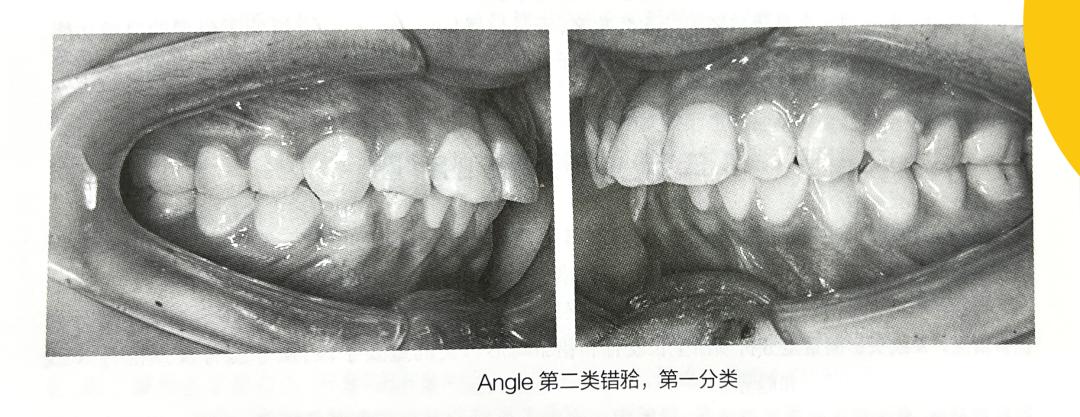

(二) Angle第二类错——远中错 (Class Ⅱ,distoclusion)

下牙弓或下颌处于远中位置,磨牙关系为远中关系。若下颌后退 1/4 个磨牙或半个前磨牙的距离,即上、下颌第一恒磨牙的近中颊尖相对时,称为轻度远中错关系。若下颌再后退,以至于上颌第一恒磨牙的近中颊尖咬合于下颌第一恒磨牙与第二前磨牙之间,则是完全的远中错关系。

第二类,第一分类 (Class Ⅱ,division 1):磨牙为远中错关系,上颌前牙唇向倾斜,表现为前牙深覆盖、深覆、牙列拥挤和开唇露齿等。

Angle第二类错——远中错 (Class Ⅱ,distoclusion) 第一分类(Class Ⅱ,division 1)